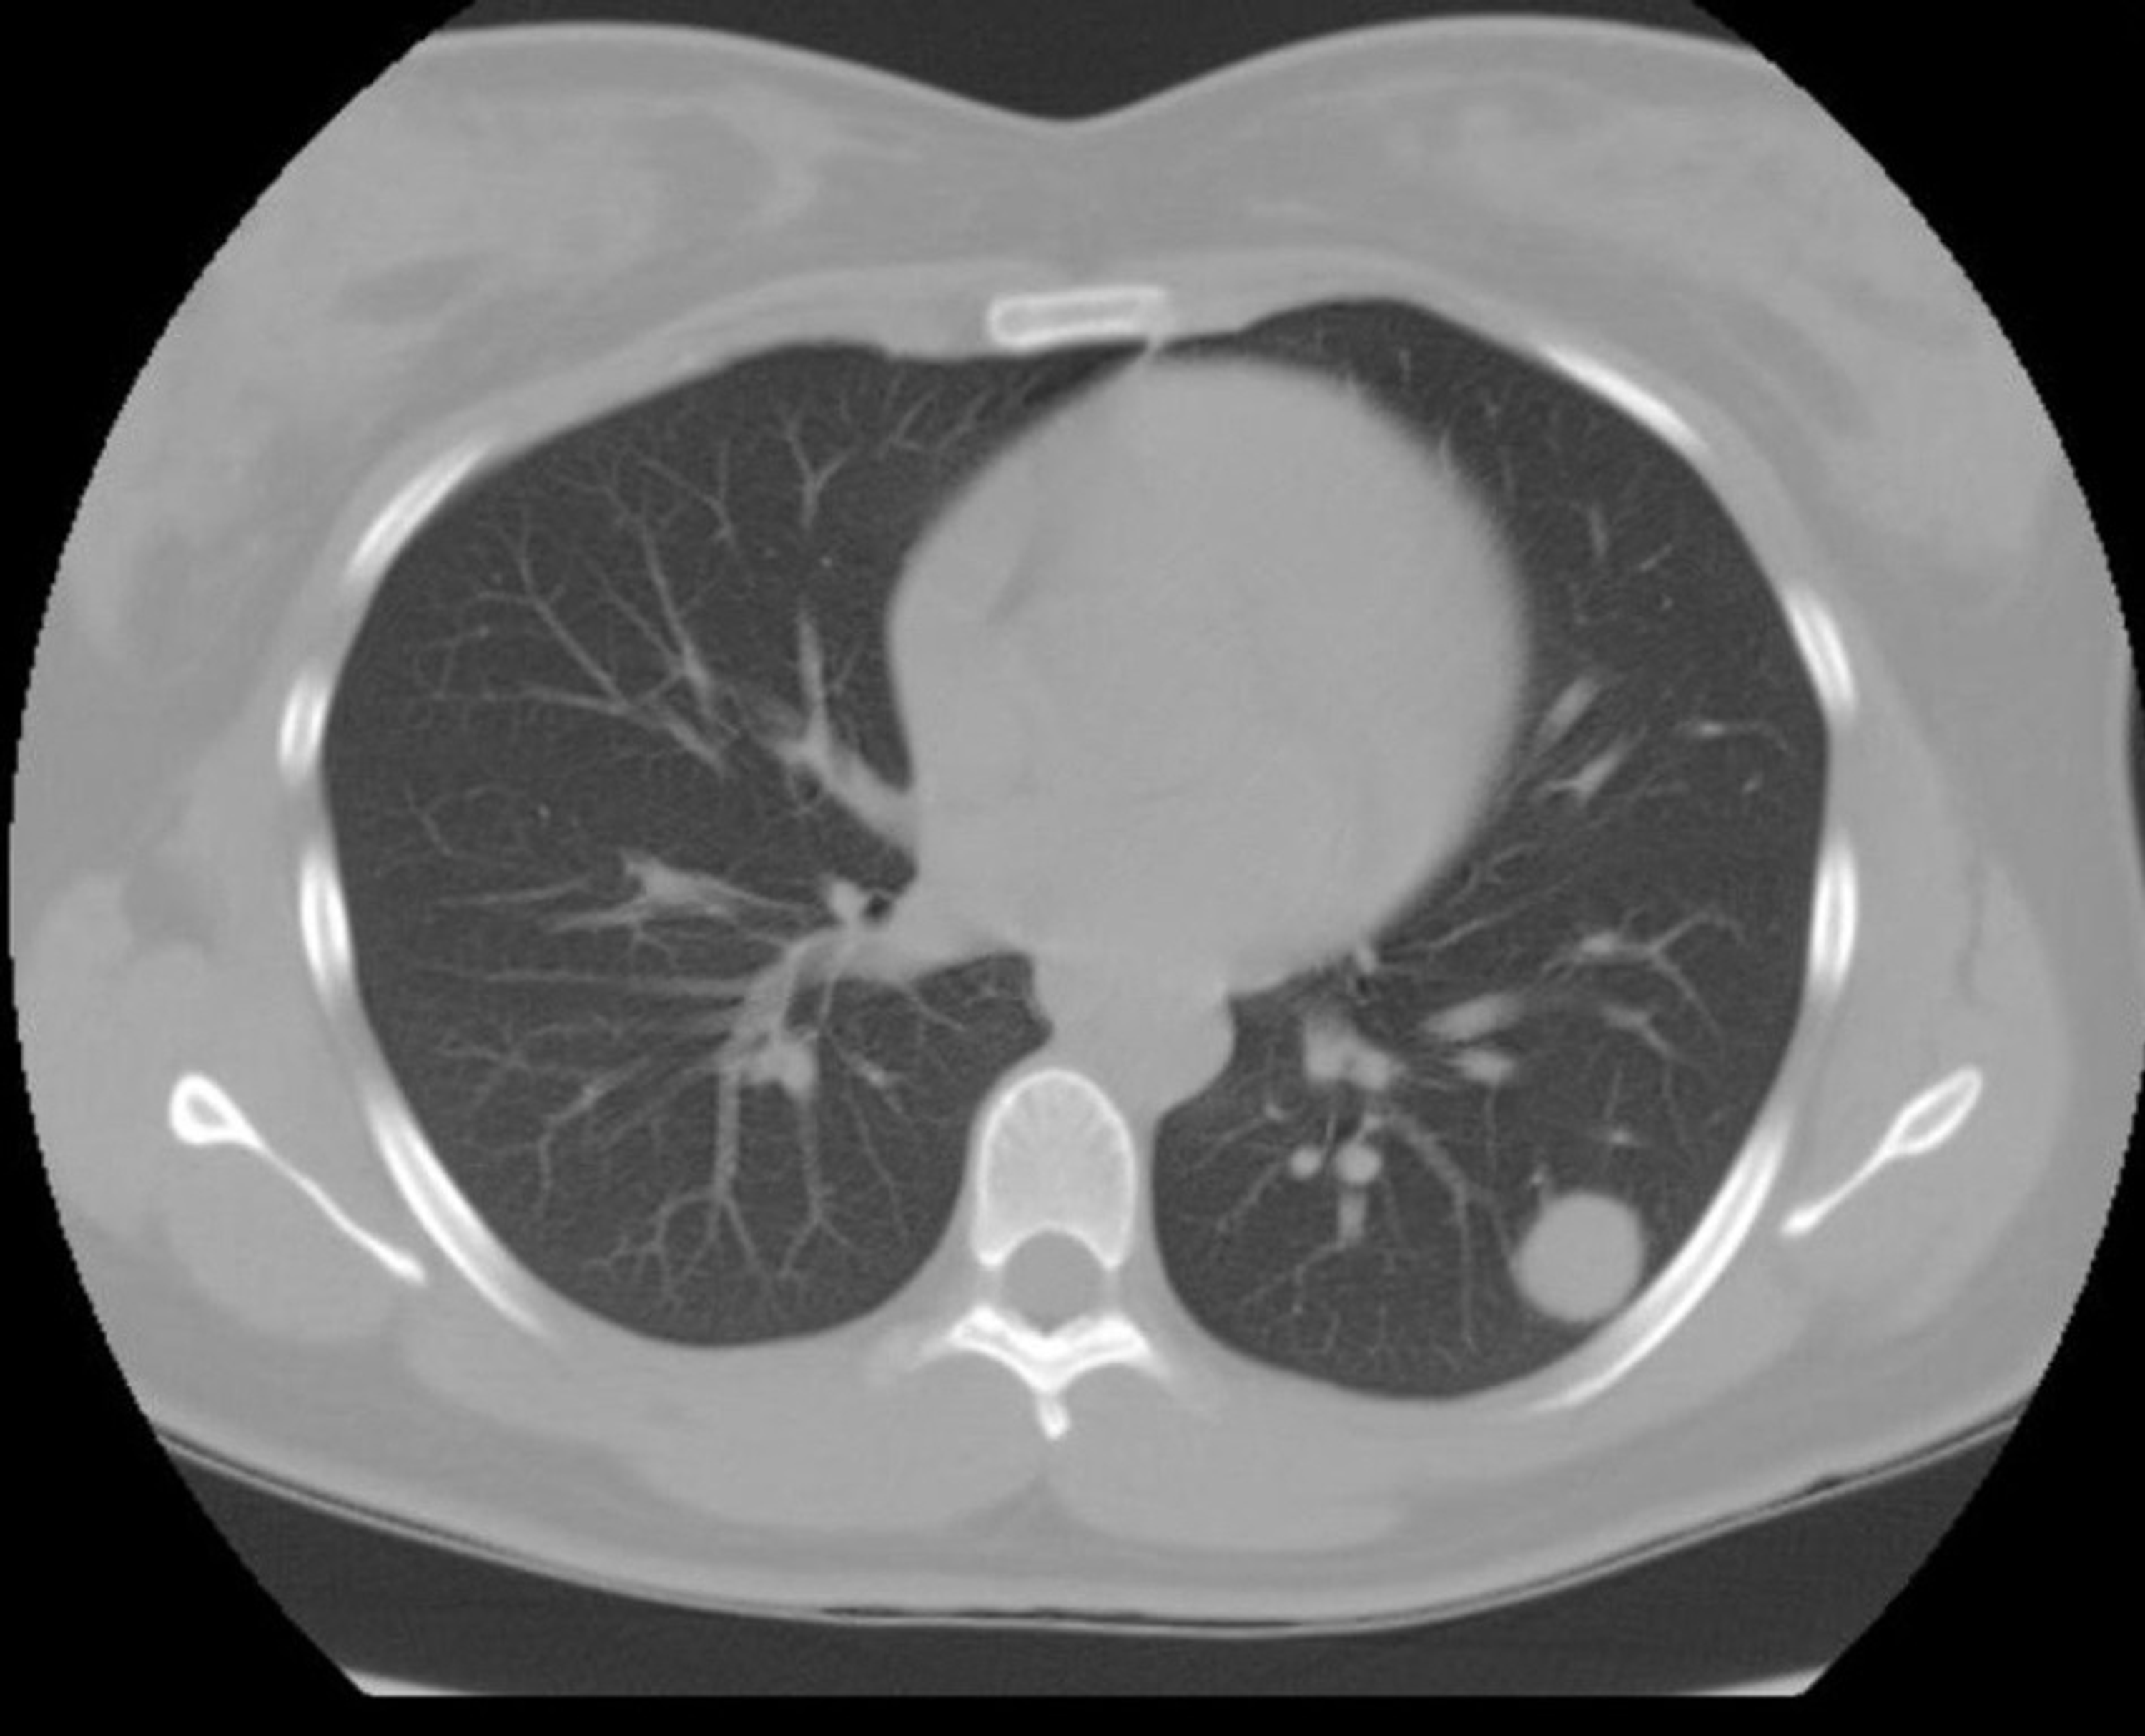

Incidental Lung Nodules on Crosssectional Imaging Radiology Key

Incidental Lung Nodules on Crosssectional Imaging Radiology Key What Is A Lung Nodule Made Of Nodules are very common and are. They're caused by various factors but usually are caused by scar tissue due to previous infections or irritants,. Lung nodules can vary in size and location within the lung. A lung nodule is a small (≤ 3 cm) abnormal area that is sometimes found during a ct scan of the chest and/or abdomen. Lung. What Is A Lung Nodule Made Of.